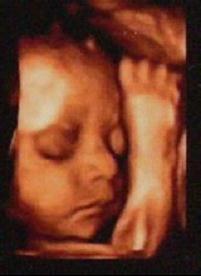

四维彩超就是四维成像技术(4D),能直观、立体显示人体器官的三维结构及动态、实时地观察立体结构,而以往的二维成像技术只能显示人体器官的某一切面。在妇产科方面,四维彩超能够对胎儿进行超声检查,能立体显示胎儿的颜面、各器官的发育情况,甚至胎儿在母体里的状态也可以观察到;对胎儿畸形,如唇裂、腭裂、骨骼发育异常、心血管畸形等能早期诊断。

准妈妈在24-30周期间做四维彩超检查最佳。

四维彩色超声诊断仪能自动为胎儿进行宫内拍“写真”和动态录像,为众多的准妈妈增添了安心和情趣。她们不再是仅仅感觉宝宝的呼吸和运动,而且可以亲眼目睹他们的一举一动和乖巧的秀容。更为重要的是,四维彩色超声诊断仪出色的人体工程学设计,不存在射线、光波和电磁波等方面的辐射,对人体的健康没有任何影响。